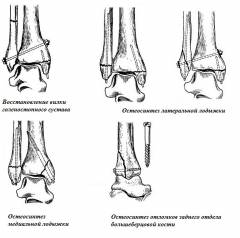

Типы операций при переломах лодыжек (рис. 10)

-

Скрепление межберцового соединения (восстановление вилки) – болт фиксируется через малоберцовую и большеберцовую кости под углом от латеральной лодыжки, дополнительно используется гвоздь для фиксации медиальной лодыжки. Все каналы формируются сверлом.

Показания к операции: перелом малоберцовой кости и медиальной лодыжки (ротационные переломы), другие переломы с разрывом межберцового соединения.

Остеосинтез латеральной лодыжки – штифт вводится через лодыжку вдоль оси малоберцовой кости, дополнительно фиксируется медиальная лодыжка с помощью гвоздя. При разрыве межберцового соединения осуществляется его скрепление.

Показания к операции: пронационные переломы.

Остеосинтез медиальной лодыжки – медиальная лодыжка фиксируется двухлопастным гвоздем под прямым углом к линии перелома. Латеральная лодыжка дополнительно фиксируется штифтом. Возможны дополнительные крепления отломков с помощью винтов.

Показания к операции: супинационные переломы.

Остеосинтез отломков большеберцовой кости – через вскрытый голеностопный сустав длинным шурупом соединяются отломки большеберцовой кости, иногда требуется дополнительный шуруп, прикрепляемый вдоль оси кости.

Показания к операции: перелом большеберцовой кости в заднем отделе дистального конца.

Рис. 10. Схематическое изображение основных типов операций при переломах лодыжек.